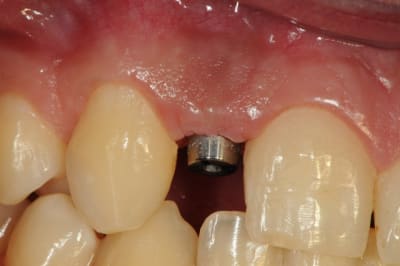

-cicatrisation de la première vis de cica,

-diamètre plus gros pour la vis de cica

- pilier pour la provisoire

- provisoire moule ION

- ajustage

- polissage soigneux

la suite tout à l'heure, ça sonne à la porte...